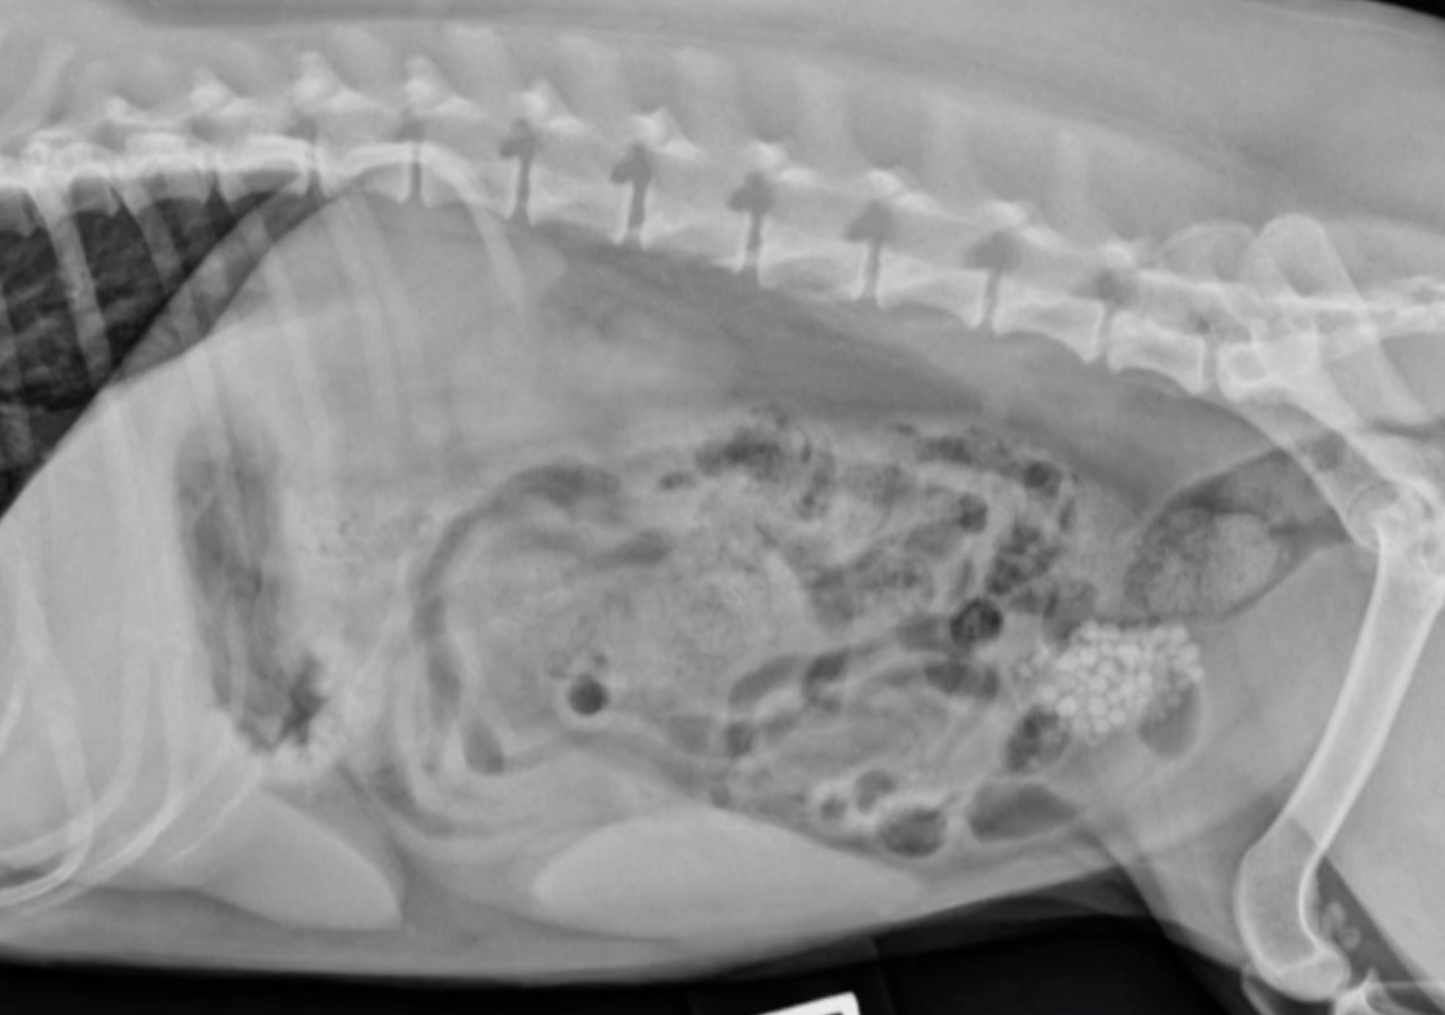

In this session we cover common canine urologic issues focusing primarily on incontinence and uroliths. Pathophysiology of canine incontinence is explored. Diagnostic algorithms are explored. Tests from those easily performed in practice to those available only at specialized practices are discussed. Treatment protocols presented. We will also covers the rocket science of canine uroliths including strategies for dealing with struvite, calcium oxylate, cystine, and urate.